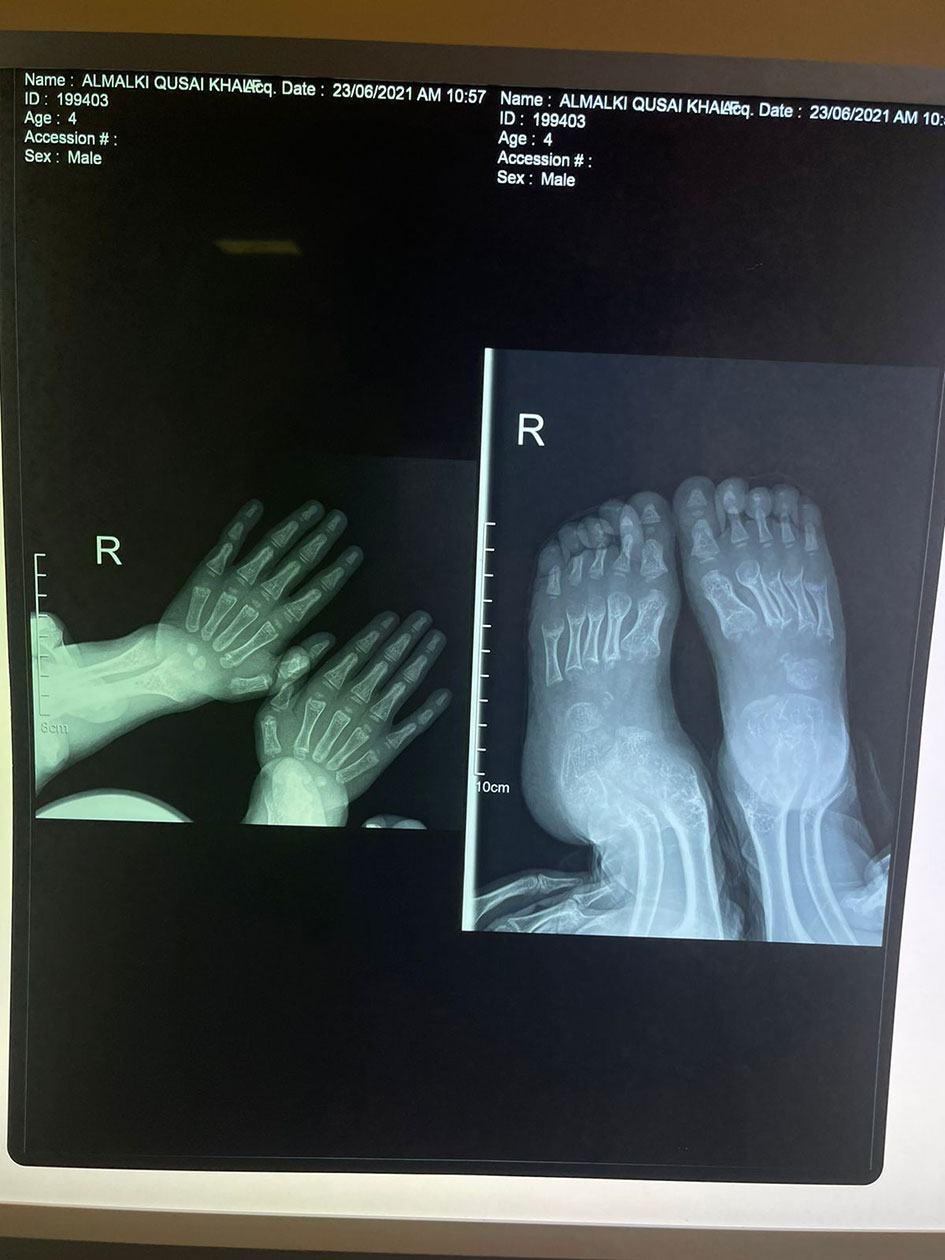

His anthropometric measurements revealed a disproportionately short stature (Figure 1), with a height of 77 cm, which was below the 1st percentile (93.6 cm), a body weight of 11 kg, which was below the 1st percentile (12.2 kg), and a borderline head circumference of 48 cm, which was over the 5th percentile (47.8 cm). Frontal bossing, rachitic rosary, wrist widening (Figure 2), scoliosis with a bent spine, and bilateral genu valgum (Figure 1), in addition to muscle hypotonia, were all visible signs of rickets. Dental caries were also discovered in the upper incisors and molar teeth (Figure 3). The following are the findings of the laboratory investigations: Serum Ca: 2.02 mmol/l, serum phosphorus: 0.84 mmol/l, Serum alkaline phosphatase: 1881IU/L, albumin 42 g/l, serum 25-OH vitamin D: 175 nmol/l, Serum Parathyroid hormone (PTH) level: 65.1 pmol/L, serum 1,25 OH D 122.4 pmol/L, Ratio of tubular maximum reabsorption rate of phosphate to glomerular filtration rate: TmP/GFR:1.5 mmol/L, urine calcium (mg/dL):urine creatinine (mmol/mmol) ratio: 0.14. Complete blood count, liver function tests and renal panel were normal. Thyroid-stimulating hormone (TSH): 5 mU/L and Free thyroxin 4 (FT4): 2.5 umol/L (Table 1). The radiological skeletal survey showed generalized osteopenia. Scoliosis with a curve on the left side (Cobb angle 44°) was present. The classic radiological features of rickets (Figure 4), broadening, cupping, and fraying of metaphyseal ends of upper and lower limb bones, were present (Figure 5). There was also a ‘rugger jersey’ appearance to the spine (Figure 6). This describes the prominent endplate densities at multiple contiguous vertebral levels to produce an alternating sclerotic-lucent–sclerotic appearance, that mimics the horizontal stripes of a rugby jersey. Vertebral insufficiency fractures of the lower dorsal vertebra were also present. Renal ultrasonography revealed no nephrocalcinosis and the kidney echogenicity was normal.

Figure 4 Fraying, splaying, widening and cupping of the metaphyseal endplates of upper and lower limb bones.